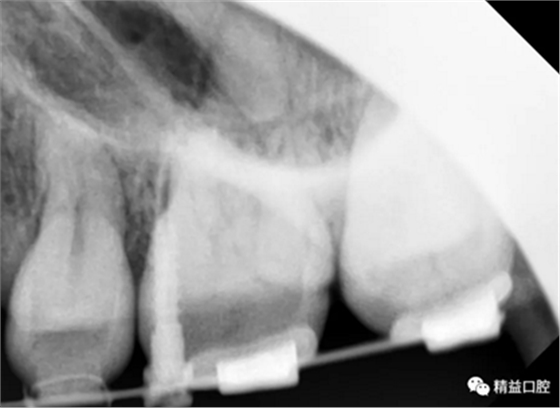

矯正前全口曲斷片

從片子上可以清除看到,上牙門牙牙根吸收非常厲害。